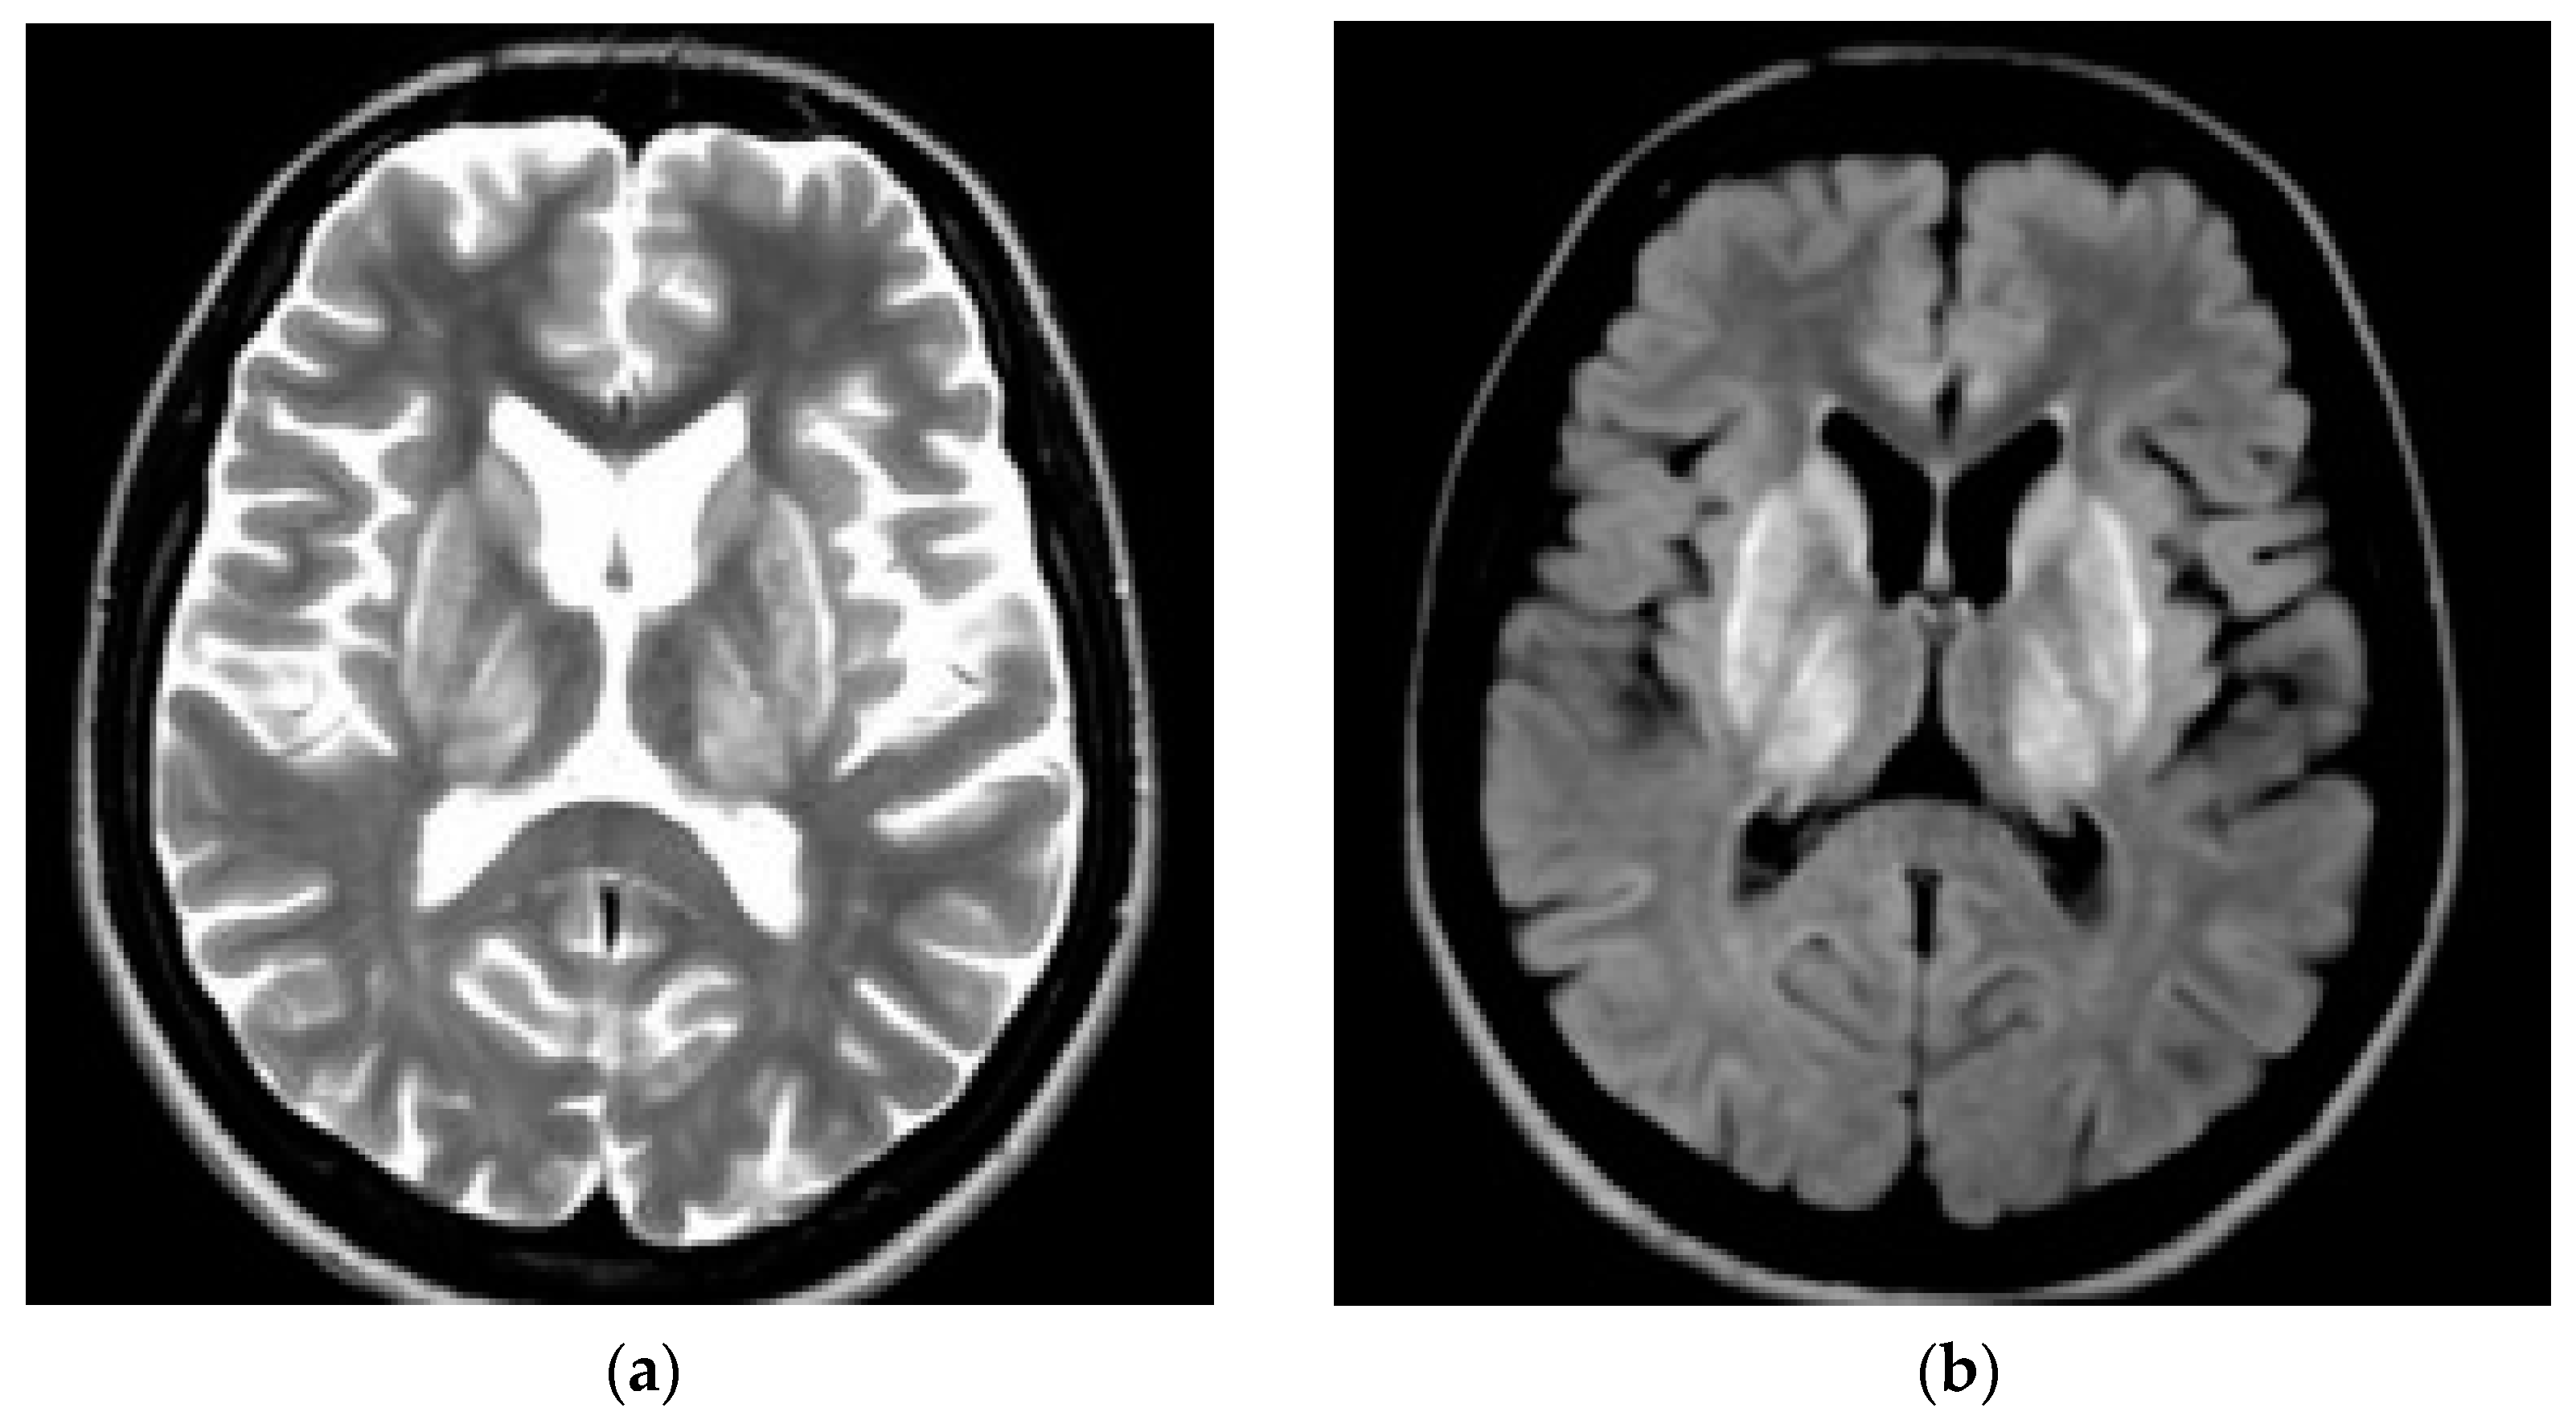

2. Wilson’s Disease—Neuropsychiatric Symptoms

3. CNS Pathology in WD—Neuroimaging Studies